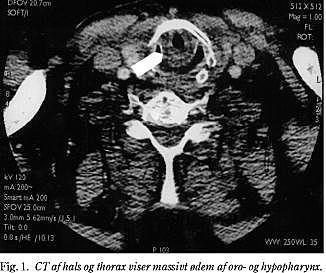

Patienten havde inspiratorisk stridor og ødematøs hals. En laryngoskopi viste blegt ødem, dette blev bekræftet af en CT (Fig. 1 ). Der blev givet adrenalin som inhalation, samt methylprednisolon og clemastin i.v. Herpå skete der en kortvarig bedring, men efter få minutter indtrådte der komplet luftvejsobstruktion og respirationssvigt. Patienten blev anæsteseret, og der blev gjort to forsøg på oral intubation med laryngoskop, samt forsøg på fiberskopisk intubation. Patienten kunne ikke maskeventileres, og det var ikke muligt at udføre nødtrakeotomi grundet ødem på den ydre hals. Endnu et forsøg på oral intubation lykkedes. Patienten fik undervejs minutter varende asystoli. Sinusrytme genetableredes efter intubation, ventilation og adrenalin i.v. Senere blev der med nogen besvær anlagt regelret trakeostomi. Steroidterapien fortsatte, og ødemet aftog over nogle dage. Patienten blev udskrevet med enkelte neurologiske skader til planlagt opfølgning i neuropsykologisk regi.